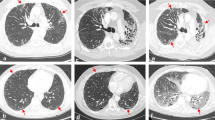

In the majority of RRP cases, the area of pneumonitis matched the irradiated area. The most common radiographic pattern of RRP on chest CT was the cryptogenic organizing pneumonia (COP) pattern, followed by the non-specific interstitial pneumonia (NSIP) pattern, the hypersensitivity pneumonitis (HP) pattern, and the acute interstitial pneumonia (AIP)/acute respiratory distress syndrome (ARDS) pattern. The radiographic patterns were associated with volume of irradiated area and the toxicity grades of RRP. AIP/ARDS was correlated with the highest grade (grade 3), then the COP pattern as grade 2, and the HP and NSIP patterns had the lowest grade 1. Ground glass opacities (GGO), reticular opacities, and consolidations were observed in some cases of RRP.